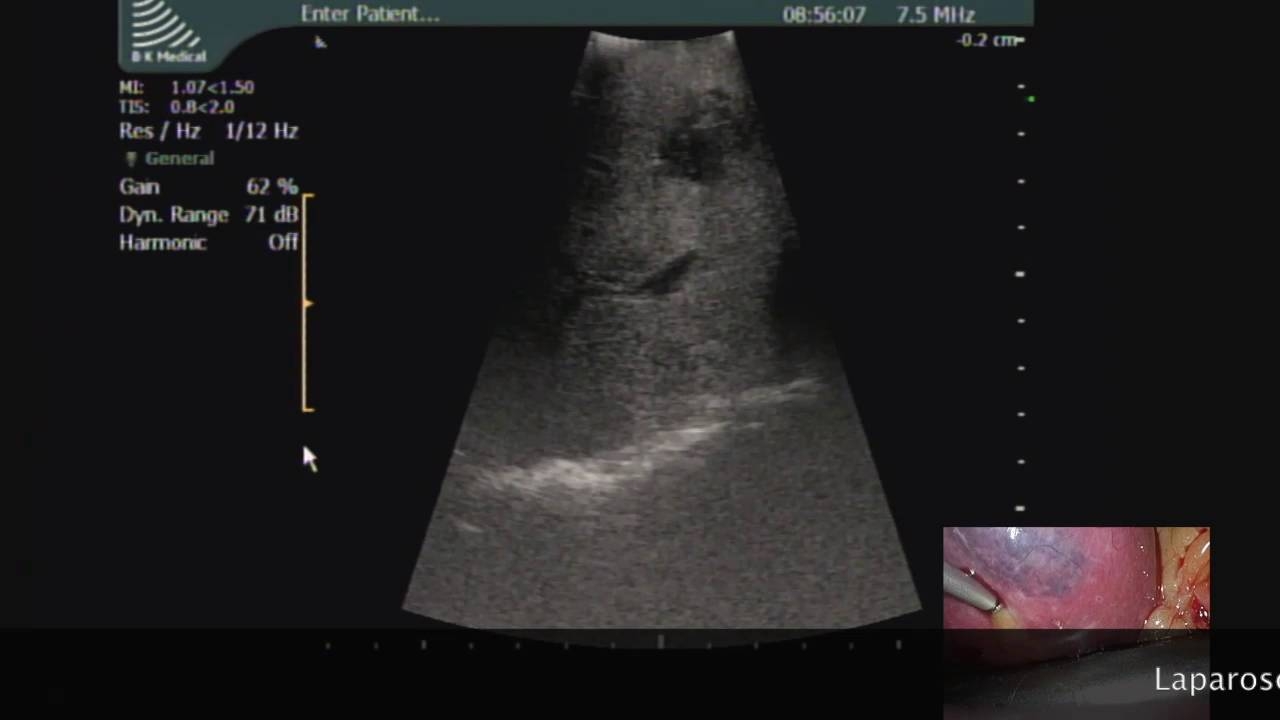

Laparoscopic MicrowaveAblation of Multiple Bilobar Liver Metastases from Ocular Melanoma

Laparoscopic Microwave Ablation of Multiple Bilobar Liver Metastases from Ocular Melanoma